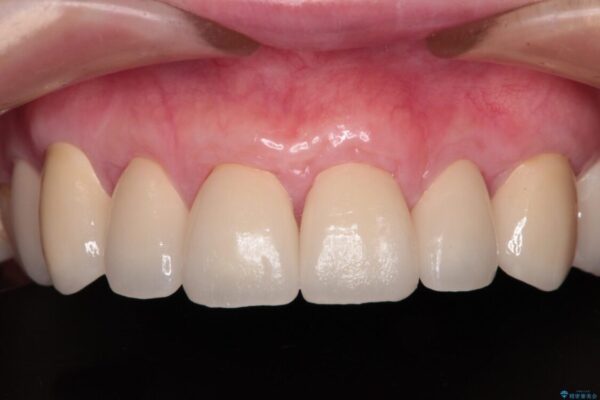

治療後について

歯肉移植術による根面被覆を行うかどうかは非常に悩まれていましたが、歯肉が覆われたことで長く見えていた歯の長さが整い、きれいな前歯の仕上がりとなりました。

治療後

• むし歯だらけの前歯をオールセラミッククラウンできれいに 治療後画像